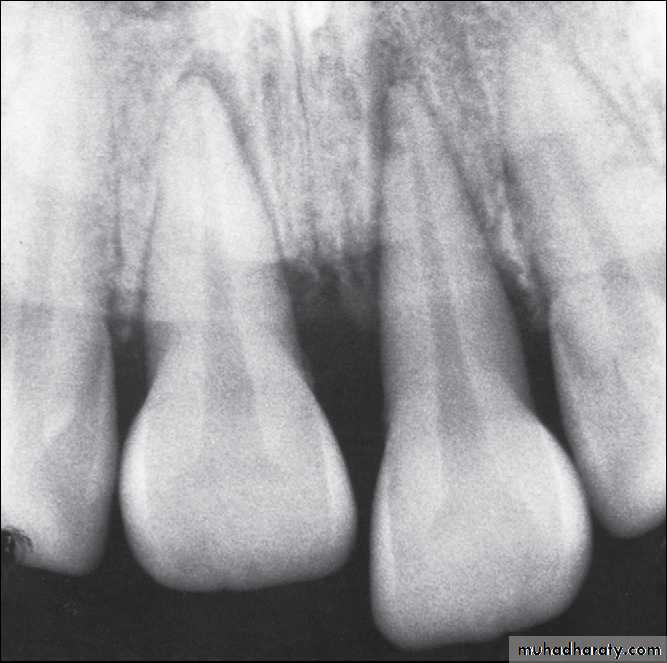

Platally displaced central and lateral incisors in apically mature tooth.

Position of teeth after digital reduction and stabilization with bonded arch wire.- Intrusion